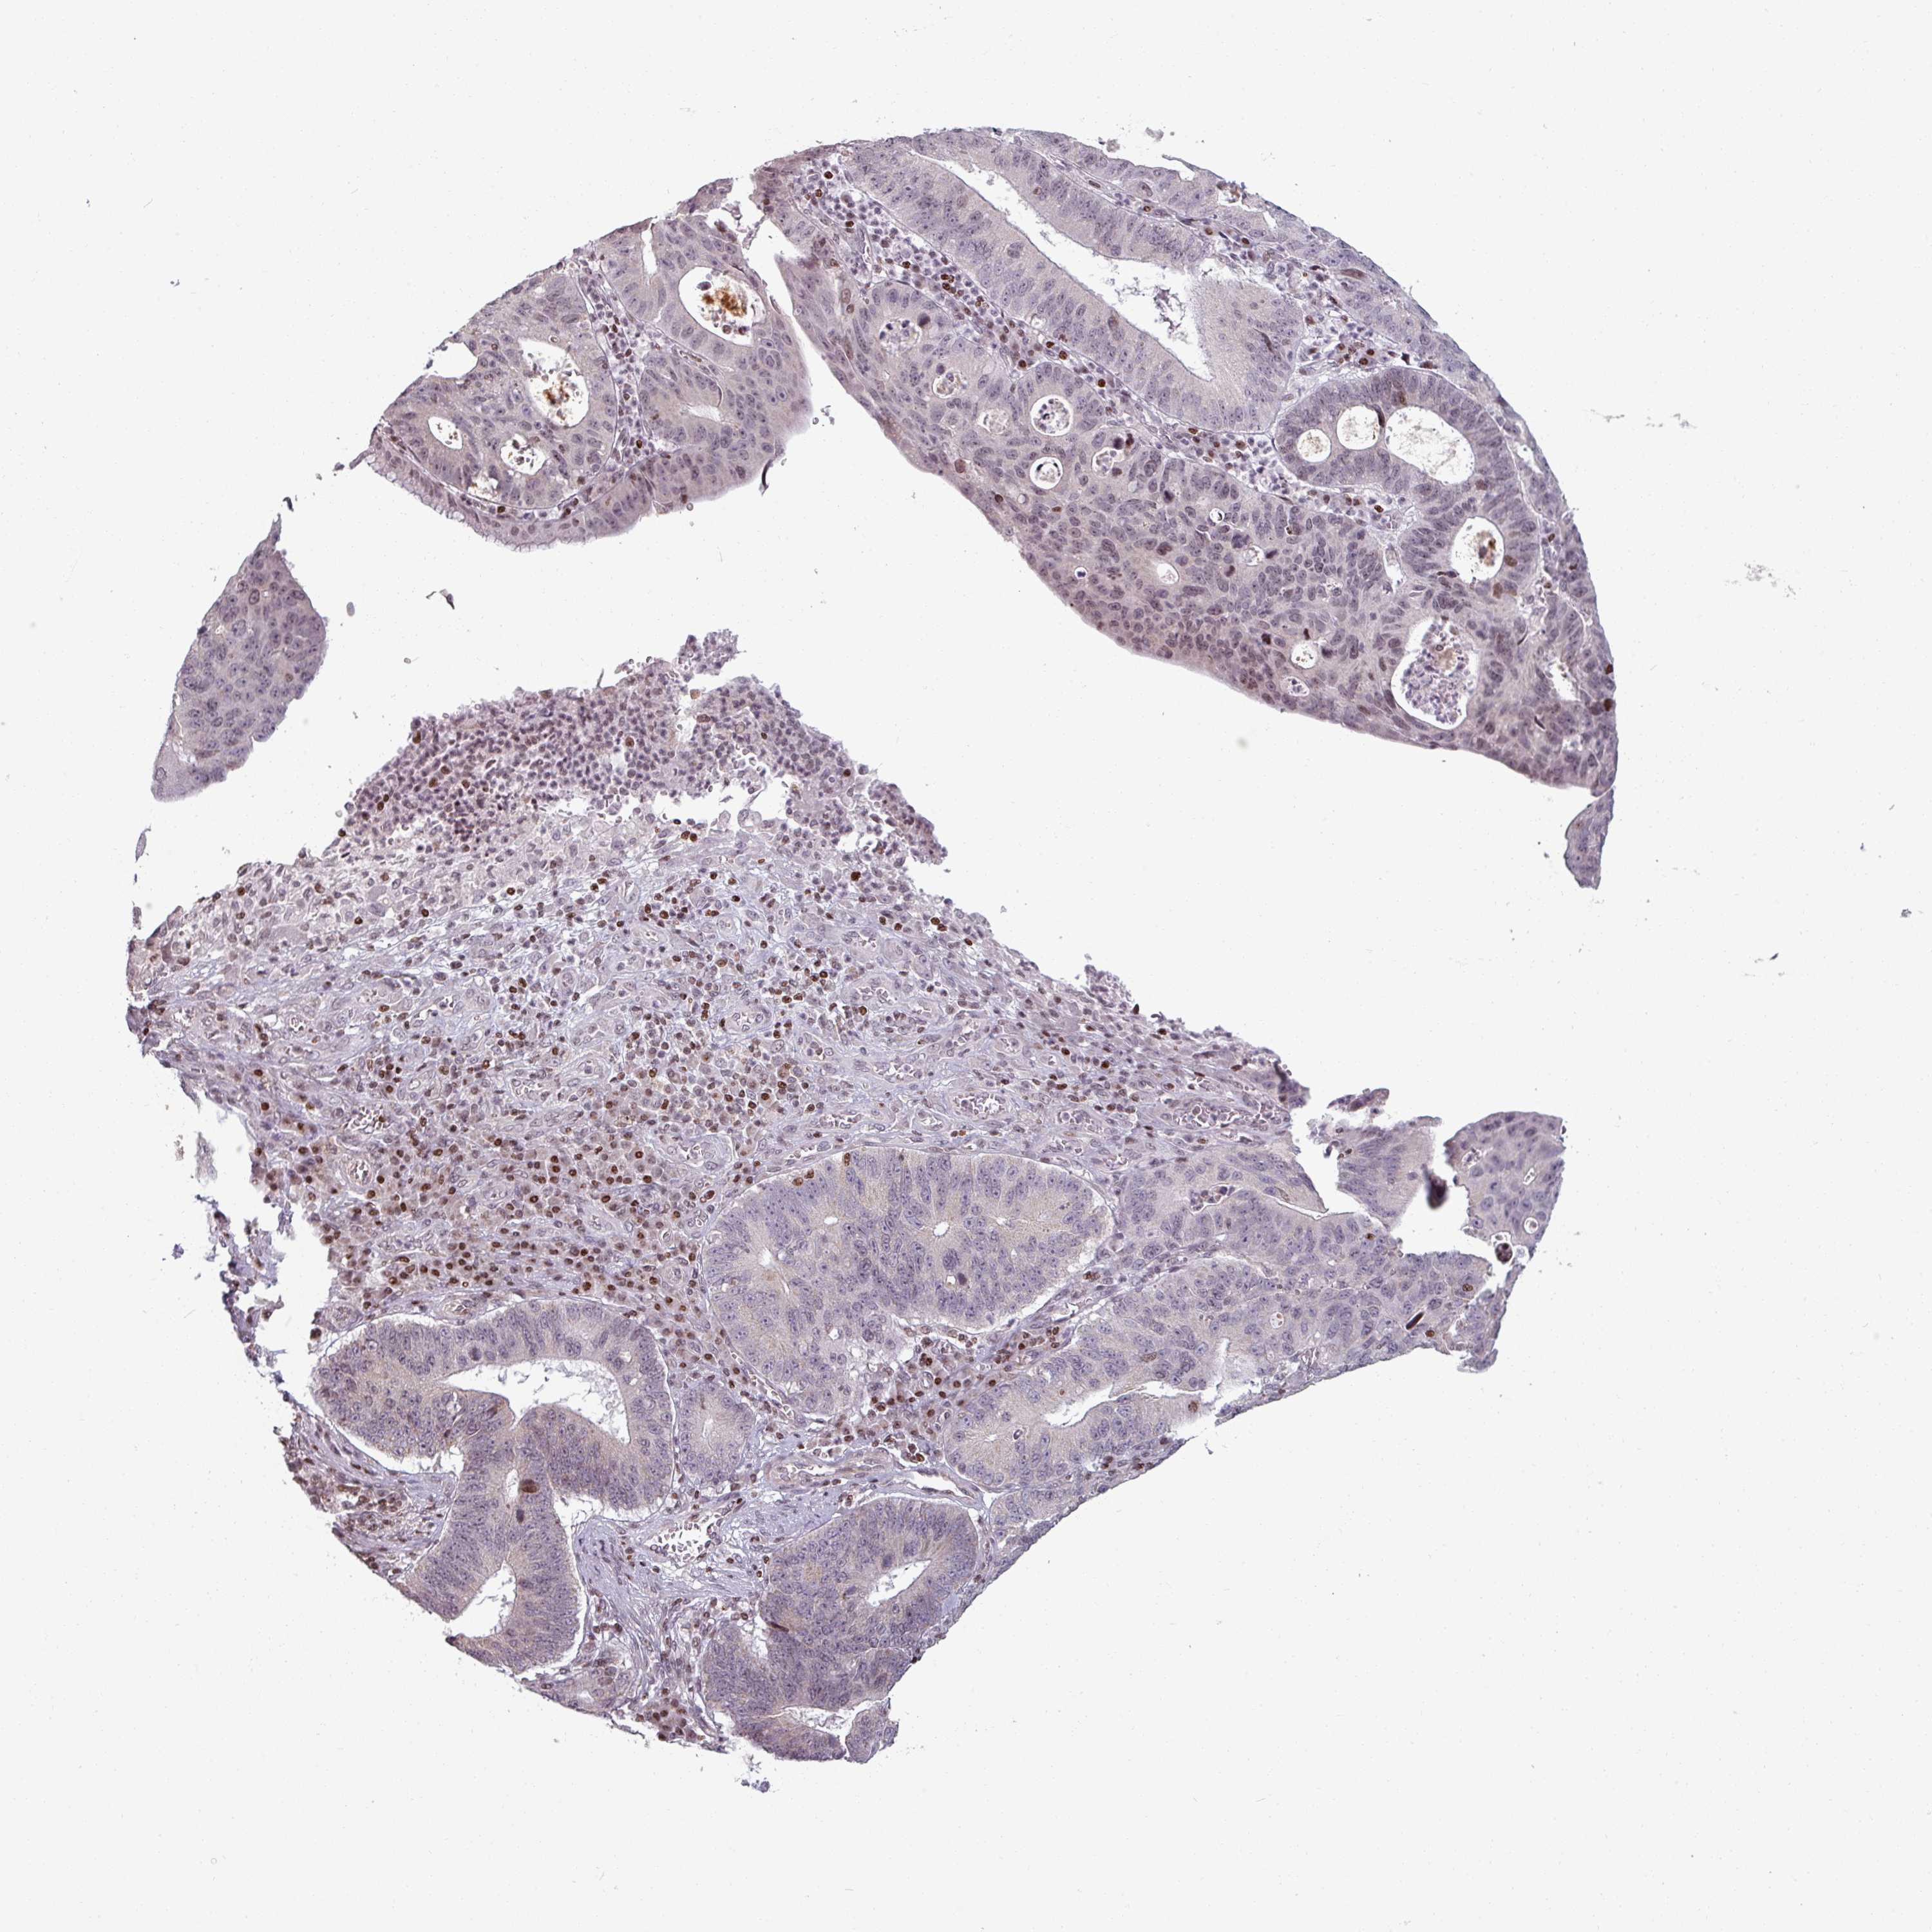

STOMACH CANCER - Protein expressioni

A mouse-over function shows sample information and annotation data. Click on an image to view it in a full screen mode. Samples can be filtered based on level of antibody staining by selecting one or several of the following categories: high, medium, low and not detected. The assay and annotation is described here.

Note that samples used for immunohistochemistry by the Human Protein Atlas do not correspond to samples in the TCGA dataset.

Antibody stainingi

Antibody staining in the annotated cell types in the current human tissue is reported as not detected, low, medium, or high, based on conventional immunohistochemistry profiling in selected tissues. This score is based on the combination of the staining intensity and fraction of stained cells.

Each image is clickable and will lead to virtual microscopy that enables deeper exploration of all samples and also displays staining intensity scores, fraction scores and subcellular localization as well as patient and tissue information for each sample.

Antibody HPA050288

Antibody HPA051168

Antibody CAB072830

Staining

Adenocarcinoma, NOS